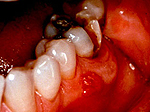

на больном зубе всегда можно обнаружить либо кариозный дефект, либо пломбу или коронку. Десна в проекции корня больного зуба обычно покрасневшая, отечная, болезненна при дотрагивании. Часто можно обнаружить, что зуб немного подвижен. В проекции корня больного зуба может также появится припухлость десны (рис.4-6) и даже припухлость мягких тканей лица.

на больном зубе опять же можно обнаружить либо кариозный дефект, либо пломбу или коронку. Периодически на десне в проекции верхушки корня больного зуба может образовываться свищевое отверстие, из которого будет выделяться скудное гнойное отделяемое (рис.6-7).